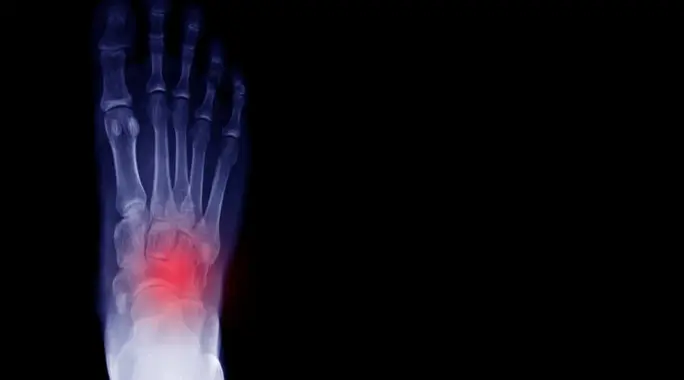

تشخيص بروز العظم الزورقي في القدم

يشكل التشخيص الدقيق حجر الزاوية في وضع خطة علاج فعالة لمتلازمة العظم الزورقي الإضافي. يعتمد الأطباء عادةً على مزيج من الفحص السريري والتصوير الطبي لتأكيد الحالة:

التصوير الطبي المتخصص

قد يطلب الطبيب إجراء بعض صور الأشعة السينية أو التصوير بالرنين المغناطيسي (MRI) لتأكيد وجود العظم الزورقي الإضافي وتحديد مدى شدة المتلازمة، وتقييم أي ضرر بالأنسجة الرخوة المحيطة.